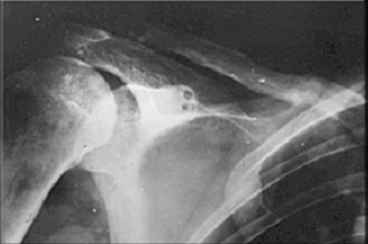

Re: Несросшийся перелом ключицы

Если заинтересует вариант фиксации трансплантата, представленный в приложении, с удовольствием поделимся опытом.